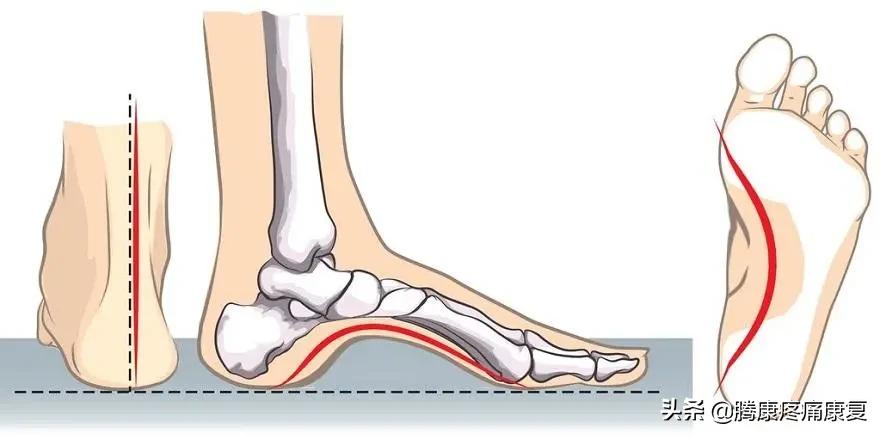

高足弓是什么

高足弓又称为弓形足,这是一种足弓异常升高的形态,当双脚均匀地站立时,由于足弓中部向上抬起,重力全部都集中在脚跟和脚掌上,最终会导致足部疼痛、鸡眼和老茧、足弓僵硬和小腿肌肉紧张。

高足弓通常是由家族遗传引起的,如果在短时间内形成了高足弓,一定要及时就诊,以查明病因。